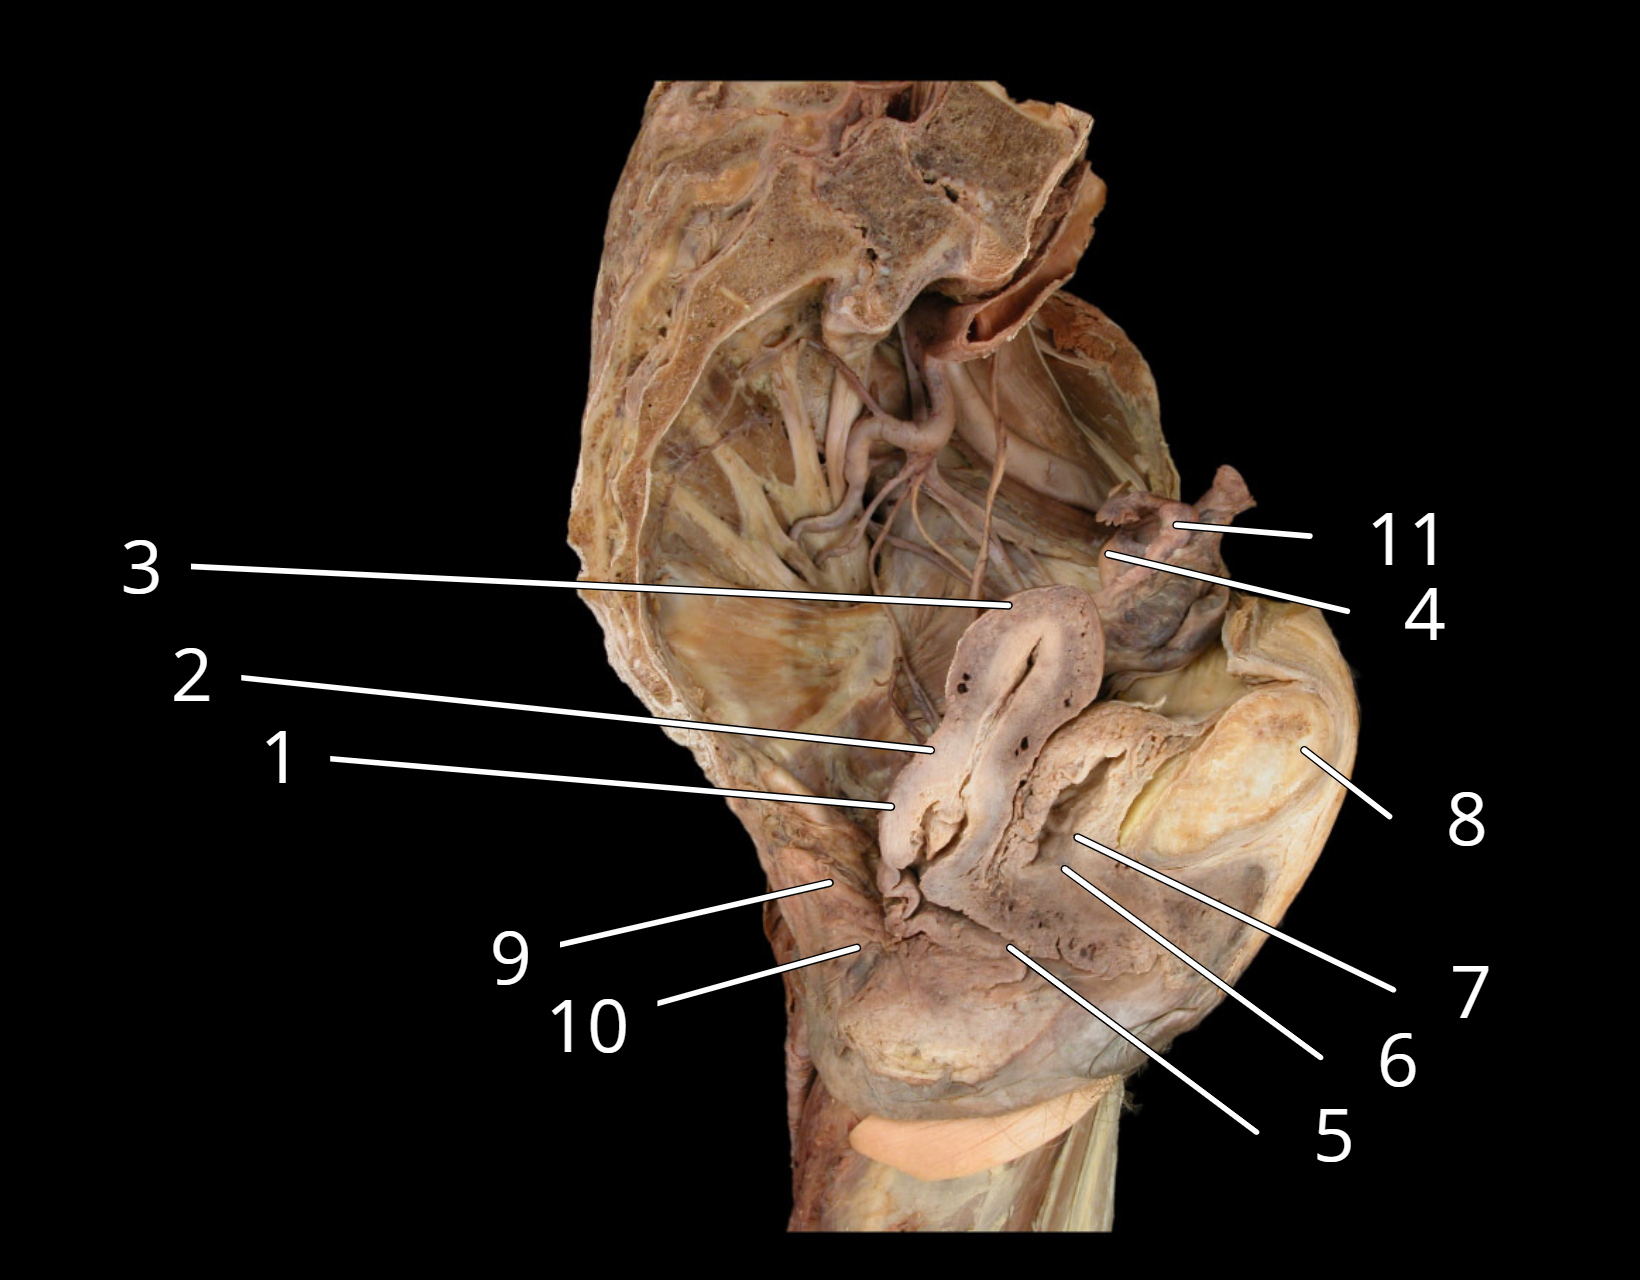

Female reproductive structures, sagittal view

1. Cervix of uterus

2. Body of uterus

3. Fundus of uterus

4. Ovary

5. Vagina

6. Urethra

7. Urinary bladder

8. Pubic symphysis

9. Rectum

10. Anus

11. Uterine tube